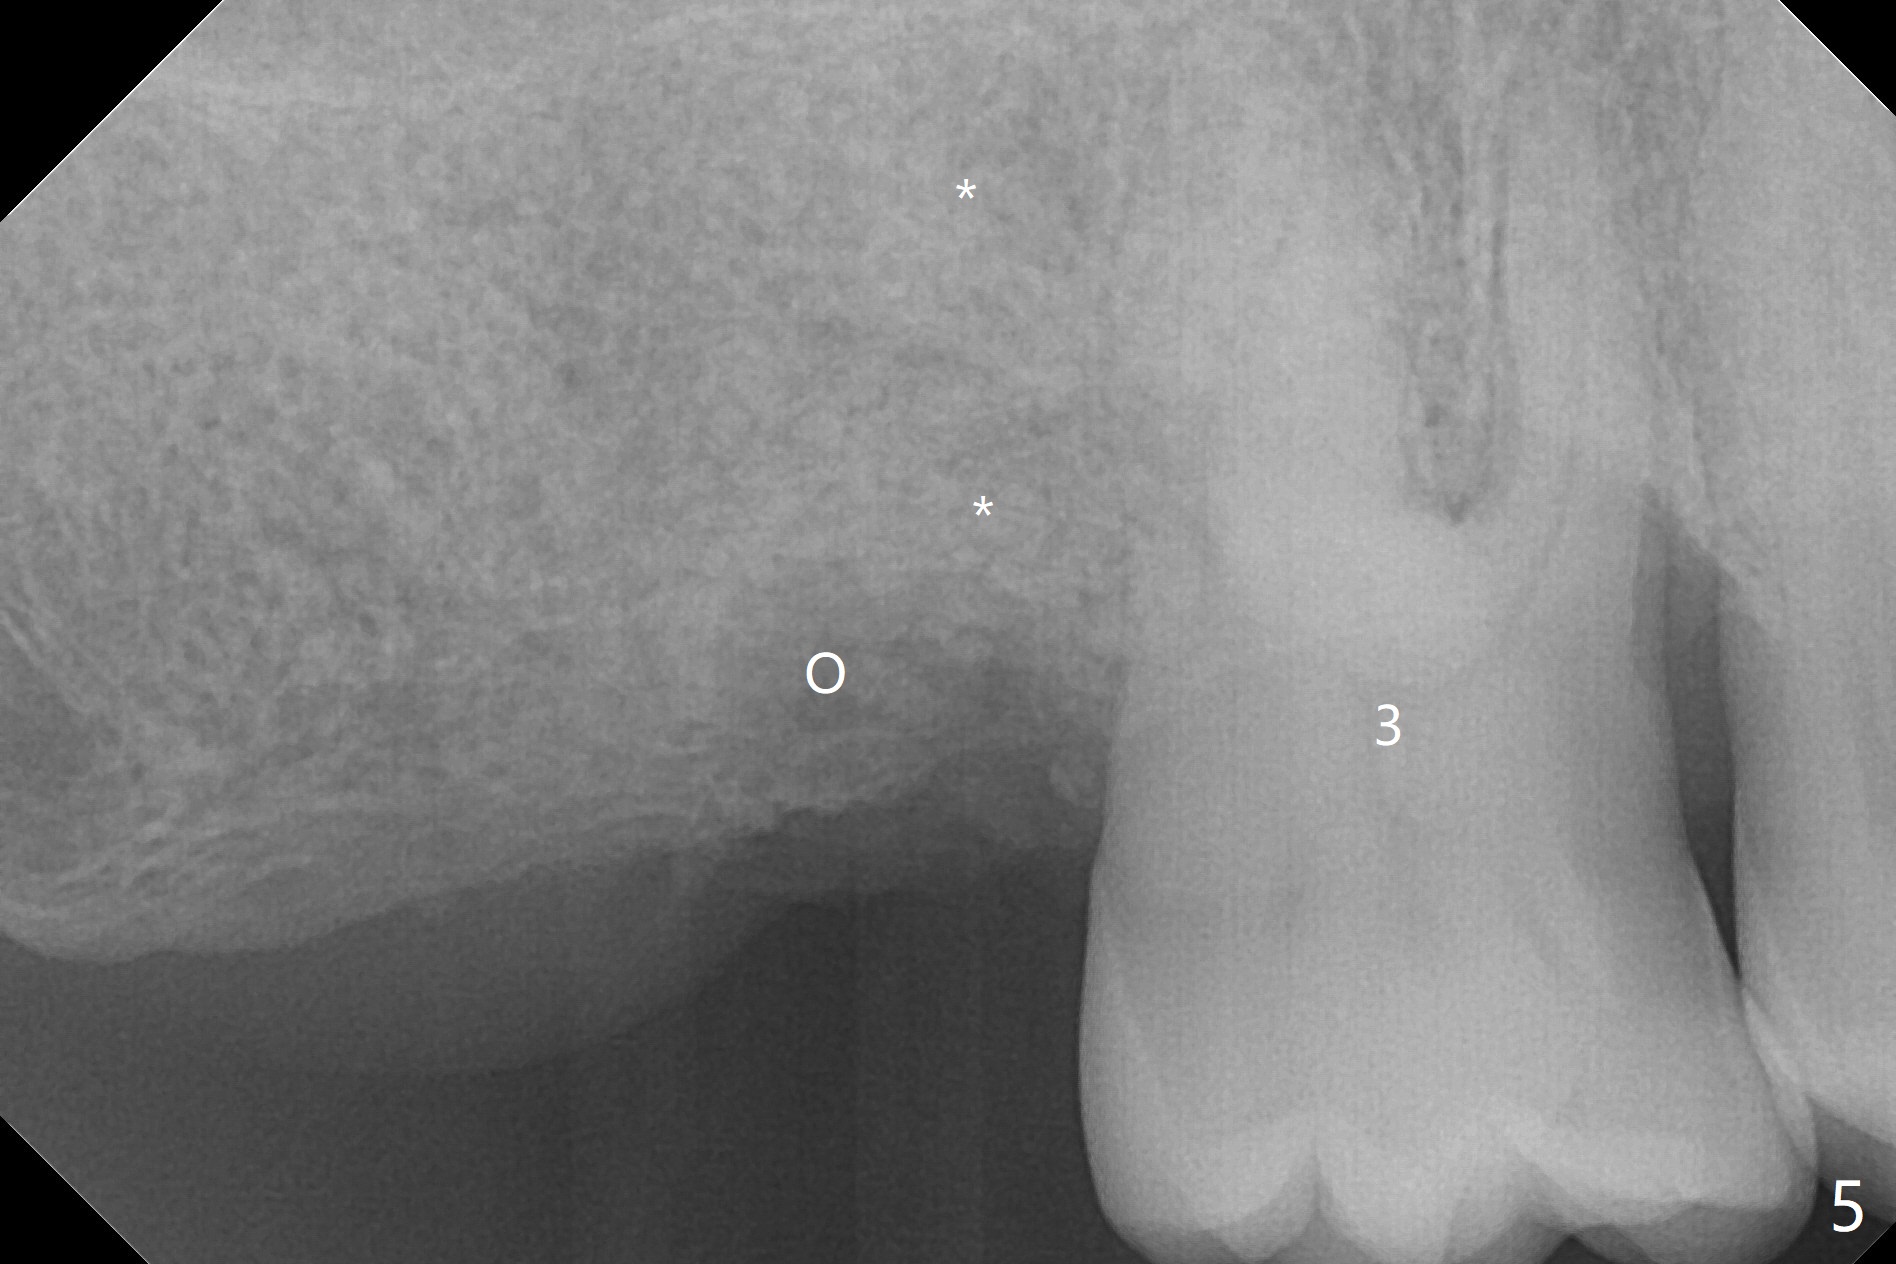

A 62-year-old man does not masticate on the right side due to facial paralysis (Fig.1 (pan taken ~ 8.5 years earlier)). Two years 9 months post #31 extraction, the tooth #2 has supraerupted (Fig.2). Nearly 7 years post extraction of #31 (Fig.3), the patient requests extraction of the supraerupted tooth because of repeated infection (Fig.4 distal view of the extracted tooth). There is calculus in the furca between the palatal (P) and buccal (B) roots. To facilitate bone regeneration in the distal surface of the tooth #3, Osteogen plug is placed in the distal portion of the socket of #2 (Fig.5 O), while allograft in the mesial one (*).